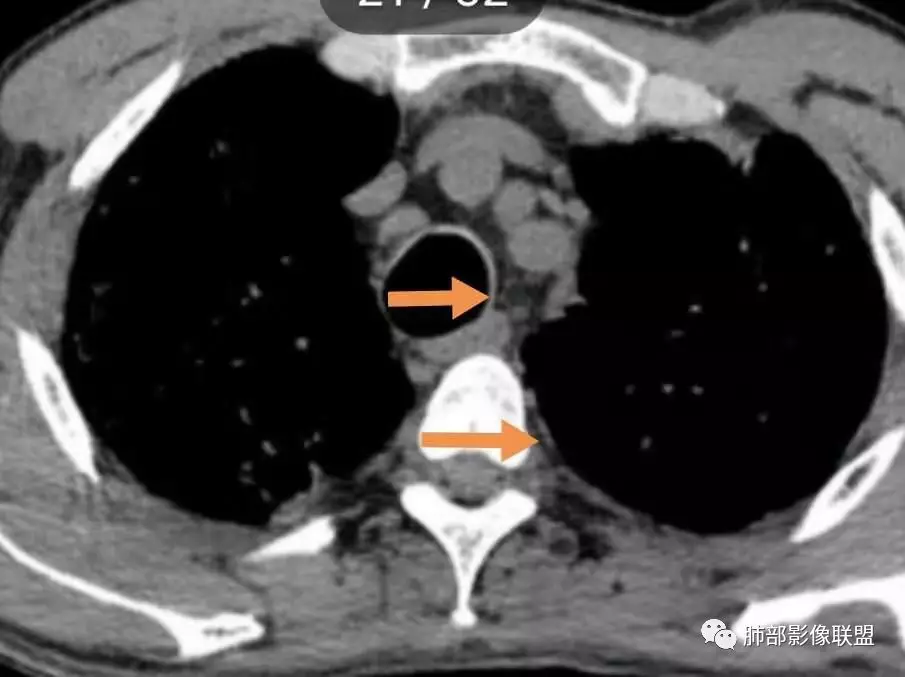

这个病例气管横径=同侧脊柱横径,需考虑气管支气管巨大症?

2. 肺气肿背景(小叶中心性肺气肿);双肺多发病灶整体沿血管支气管束及胸膜下分布,以上叶及下叶背段分布为主,有实变及GGO,边界清楚,有树芽,小叶间隔及中央间质增厚,叶间裂见到多发结节,部分支气管不规则牵拉扩张,提示病灶纤维化明显,结合临床病史,考虑病灶为间质性感染,肺门及纵隔内有钙化淋巴结,小叶间隔结节,考虑淋巴道增值性疾病可能,综合常规要怀疑间质性肺结核。